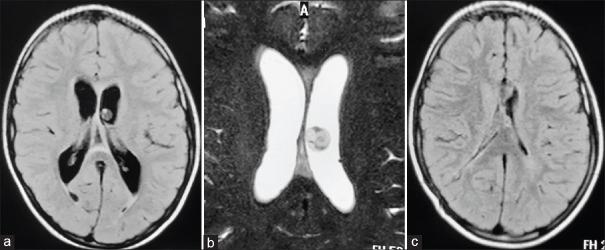

对2010年至2018年间接受内镜治疗的26例IVNCC患者的临床记录和随访进行回顾性分析。IVNCC的诊断基于脑部增强磁共振成像。通过额部钻孔进行0°内镜经颅内镜检查。进行第三脑室造瘘术并用血管导管切除囊尾蚴囊肿。

结果

第三脑室内囊肿的脑室内囊肿切除成功率,无论是完全切除还是部分切除,均为100%(14/14);第四脑室内囊肿为62.5%(5/8);侧脑室内囊肿为100%(4/4)。内镜下囊肿切除的总体成功率为88.46%。88.46%的病例成功建立了CSF流动通路。平均随访时间为44个月,所有患者在随访期间均无症状。